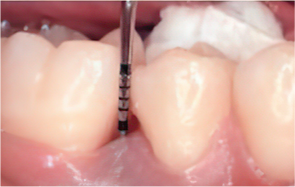

엠도게인 수술과정

STEP 01

잇몸을 절개

STEP 02

Scaling Root Planning을 실시

-

STEP 03

치석 및 치태 등 제거

STEP 04

엠도게인 도포

STEP 05

클렌징

STEP 06

판막을 봉합